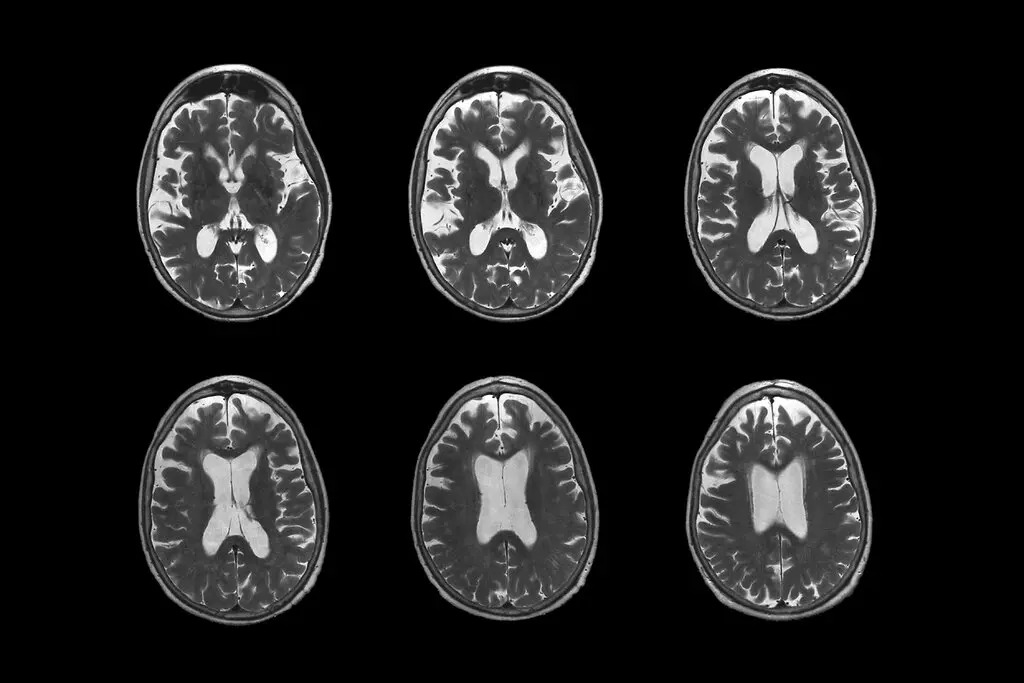

ABD Gıda ve İlaç Dairesi, Alzheimer'ı yavaşlattığı gözlenen yeni ilacı onayladı

Houston, 7 Ocak 23 (TAK): ABD Gıda ve İlaç Dairesi (FDA), Alzheimer hastalığını yavaşlattığı görülen yeni bir ilacı onayladı.